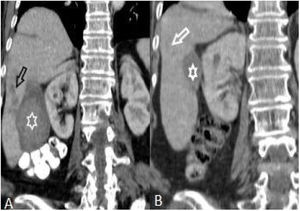

(A and B): Hepatomegaly, splenomegaly (asterisk), enlarged portal and splenic veins (black arrow), subcapsular hypodense area (circles), and intrahepatic biliary dilatation/thickening in segment VI (white arrow) in a 46-year-old woman (A). Changes of the findings on post-treatment scan are seen in (B).

The number of patients with hepatomegaly at the first admission was significantly higher than after treatment (p<.05). But the difference of the number of patients with splenomegaly was not significant (Table 2) (Fig. 1).

After treatment, the complete recovery of liver lesions was detected in 18 patients. Patchy hypodense areas were seen in 7 patients, microtubular abscess in 6 (Fig. 2), sequele calcification in 4, and abscess larger than 3cm in remained one patient (Fig. 3). The incidence of microtubular abscess and abscess >3cm was significantly lower in post-treatment images (p<.05). But, a non-significant increase in patchy hypodense area incidence was found on post-treatment images (Table 2).

CT is the best imaging modality to detect the intrahepatic and extrahepatic findings and the complications of the lesions in the early and late stages of the disease with high sensitivity.4 In literature, hepatomegaly and splenomegaly are documented findings in patients with fascioliasis.13 In our study, we observed hepatomegaly in 18 (50%) and splenomegaly in 8 (22.2%) patients before treatment. We found a significant decrease in the number of patients with hepatomegaly (n:10, 27.7%) (p: .027) and also a mild decrease in the number of patients with splenomegaly (n:7, 19.7%) (p: .385) after treatment. Also, the average craniocaudal length of the liver and spleen of the patients diminished markedly after the treatment. As there was no study in literature on the portal and splenic vein diameter changes in the patients with fascioliasis after treatment, we measured the diameters before and after treatment. We observed a mild decrease in the diameter of portal vein and a significant decrease in splenic vein after the treatment.